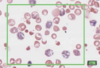

What is this slide stained with?

What stains:

- Purple

- Red/pink

- Pale blue

- Dark blue

Purple = chromatin/nuceli and netrophil granules

Red/pink = Erythrocytes/eosin granules

Pale blue = Lymphocyte/monocyte plasma

Dark blue/purple = Basophil granules